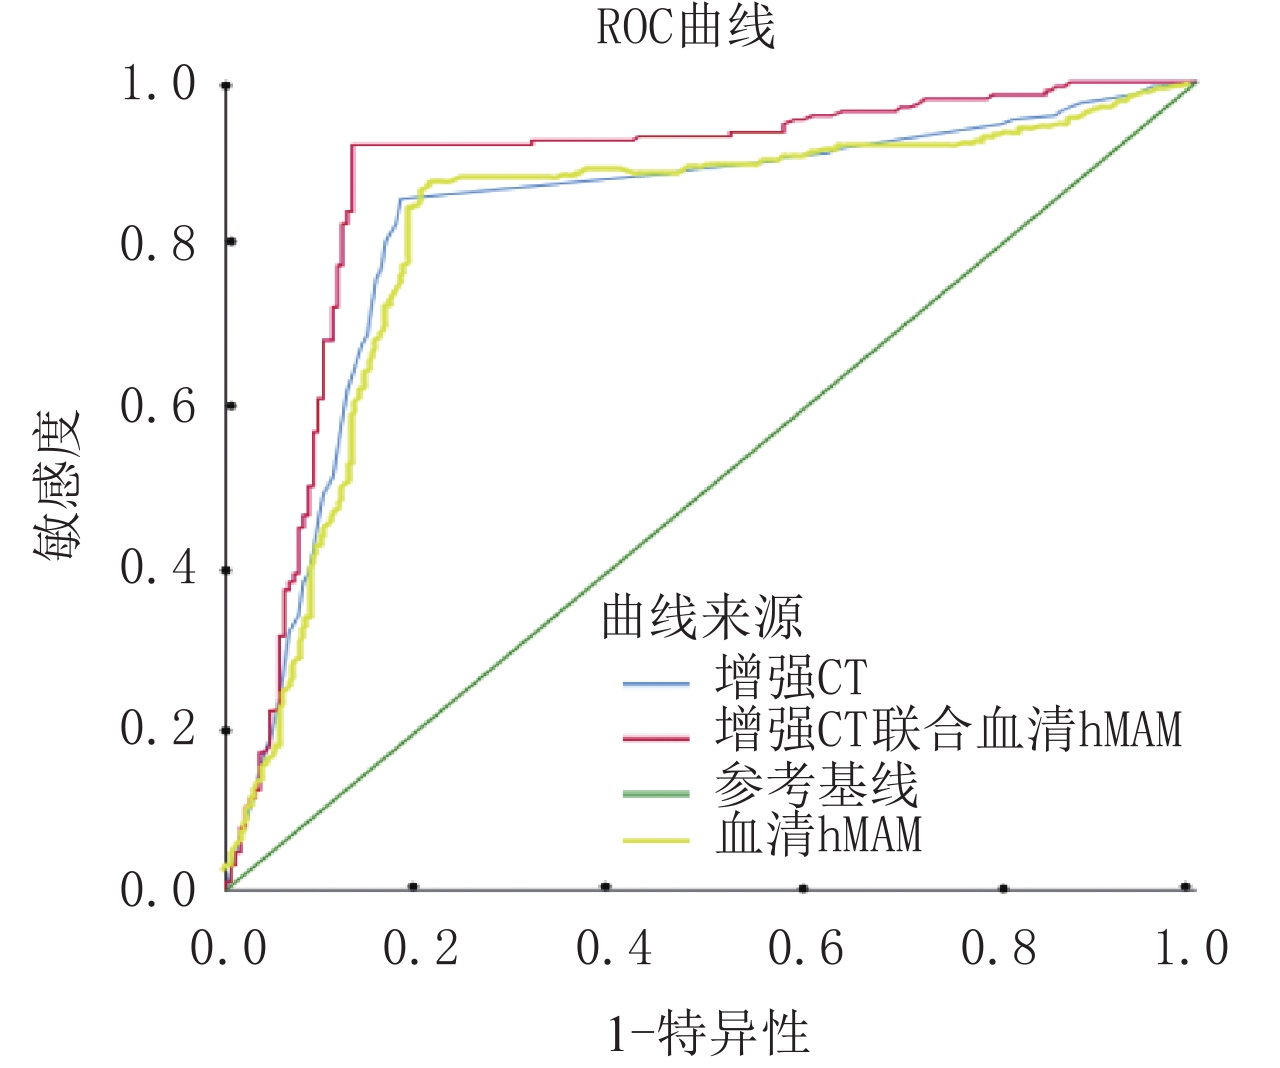

目的:探讨增强CT联合血清人乳腺珠蛋白(hMAM)水平检测对乳腺癌腋窝淋巴结转移的诊断价值。方法:选取2017年6月至2020年6月之间我院就诊并行手术治疗的乳腺癌患者100例,所有患者术前均行增强CT,并检测血清hMAM水平,以术后病理结果为标准,比较增强CT、血清hMAM水平单独检查及联合检查对腋窝淋巴结转移的检出率,分析其与病理结果的一致性,进一步分析增强CT联合血清hMAM水平对乳腺癌腋窝淋巴结转移的诊断价值。结果:血清hMAM和病理结果共同诊断为腋窝淋巴结转移阳性的患者51例(51%),血清hMAM和病理结果共同诊断为腋窝淋巴结转移阴性的患者12例(12%),一致率81.5%,Kappa检验一致性良好;增强CT和病理结果共同诊断为腋窝淋巴结转移阳性的患者55例(55%),增强CT和病理结果共同诊断为腋窝淋巴结转移阴性的患者13例(13%),一致率82.3%,Kappa检验一致性良好;增强CT联合血清hMAM检查和病理结果共同诊断为腋窝淋巴结转移阳性的患者61例(61%),增强CT联合血清hMAM检查和病理结果共同诊断为腋窝淋巴结转移阴性的患者16例(16%),一致率90.4%,Kappa检验一致性良好;增强CT和血清hMAM对淋巴结转移检出的灵敏度分别78.0% 和76.5%,特异度分别69.5% 和70.3%,差异不具有显著性,增强CT联合血清hMAM对淋巴结转移检出的灵敏度、特异度明显高于两者单独检查,差异具有统计学意义。结论:增强CT联合血清hMAM水平对乳腺癌腋窝淋巴结转移具有较高的诊断价值,和病理结果比较一致性高,乳腺癌术前综合检查、全面分析,有利于疾病的诊断,对于手术方式的选择提供依据。

Abstract:Objective: To investigate the diagnostic value of enhanced CT combined with serum human mammaryglobin (hMAM) level in detection of axillary lymph node metastasis of breast cancer. Methods: 100 patients with breast cancer treated in our hospital from June 2017 to June 2020 were selected. All patients underwent enhanced CT before operation, and the serum hMAM level was detected. We further analyzed the diagnostic value of enhanced CT combined with serum hMAM level in axillary lymph node metastasis of breast cancer by comparing the consistency between the results of the detection rate of axillary lymph node metastasis obtained respectively by enhanced CT, serum hMAM level, combined examination and the postoperative pathological results which was taken as the standard. Results: 51 patients (51%) were diagnosed as positive axillary lymph node metastasis by serum hMAM and pathological results while 12 patients (12%) with negative axillary lymph node metastasis were diagnosed by both serum hMAM and pathological results, with the consistency rate of 81.5%. Kappa test showed great consistency, 55 cases (55%) were diagnosed as positive axillary lymph node metastasis by enhanced CT and pathological results while 13 cases (13%) with negative axillary lymph node metastasis were diagnosed by enhanced CT and pathology, with the consistency rate of 82.3%. Kappa test showed great consistency, There were 61 cases (61%) with positive axillary lymph node metastasis diagnosed by enhanced CT combined with serum hMAM examination and pathological results while 16 cases (16%) with negative axillary lymph node metastasis diagnosed by enhanced CT combined with serum hMAM examination and pathological results, with the consistency rate of 90.4%. Kappa test showed great consistency, The sensitivity of enhanced CT and serum hMAM were respectively 78.0% and 76.5% while the specificity were respectively 69.5% and 70.3%, which showed no significant difference. The sensitivity and specificity of enhanced CT combined with serum hMAM in detecting lymph node metastasis were significantly higher than those of the two alone. Conclusion: The method of enhanced CT combined with serum hMAM level hold high diagnostic value for axillary lymph node metastasis of breast cancer, and show high consistency with the pathological results. Preoperative comprehensive examination and comprehensive analysis of breast cancer are conducive to the diagnosis of the disease and can provide basis for the selection of surgical methods.

病理 增强 CT 联合血清 hMAM 一致率/% K P 阳性/例 阴性/例 腋窝淋巴结阳性 61 17 90.4 0.757 0.000 腋窝淋巴结阴性 6 16 5 增强CT和血清hMAM对淋巴结转移灵敏度及特异度对比(

$\bar x \pm s $ )组别 增强 CT 血清 hMAM 增强 CT 联合血清 hMAM t P 灵敏度/% 78.0 76.5 88.7 6.32 0.061 特异度/% 69.5 70.3 83.5 表 5 增强CT和血清hMAM对淋巴结转移灵敏度及特异度对比(

$\bar x \pm s $ )Table 5 Comparison of sensitivity and specificity between enhanced CT and serum hMAM for lymph node metastasis (

$\bar x \pm s $ )组别 增强 CT 血清 hMAM 增强 CT 联合血清 hMAM t P 灵敏度/% 78.0 76.5 88.7 6.32 0.061 特异度/% 69.5 70.3 83.5 -